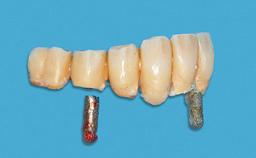

An 83-year-old man presented together with his caregiver at the dental department of the Medical University of Innsbruck, Austria with complaints of swelling in the right maxillary canine area and loss of retention of his 5-years-old mandibular denture. The patient had a significant medical history (20 years) of bipolar affective disorder with moderate depression (F 31.3) and dementia in Alzheimer’s disease (F 00.2). The patient had been in ambulant psychiatric therapy for his depressive illness for the past 20 years. He lived alone and had no children; his sister assisted with daily living. She reported that the patient exhibited compulsive hoarding behavior. In the previous two months, she had noted increasing disorientation and vertigo in the patient. She therefore accompanied him for a medical consultation at the Department of Psychiatry and Psychotherapy of the Medical University of Innsbruck. He was released home after a 6-week inpatient stay.

Prosthesis Type RDP

Defining Characteristics Fully edentulous lower jaw to be rehabilitated with an implant-borne removable overdenture